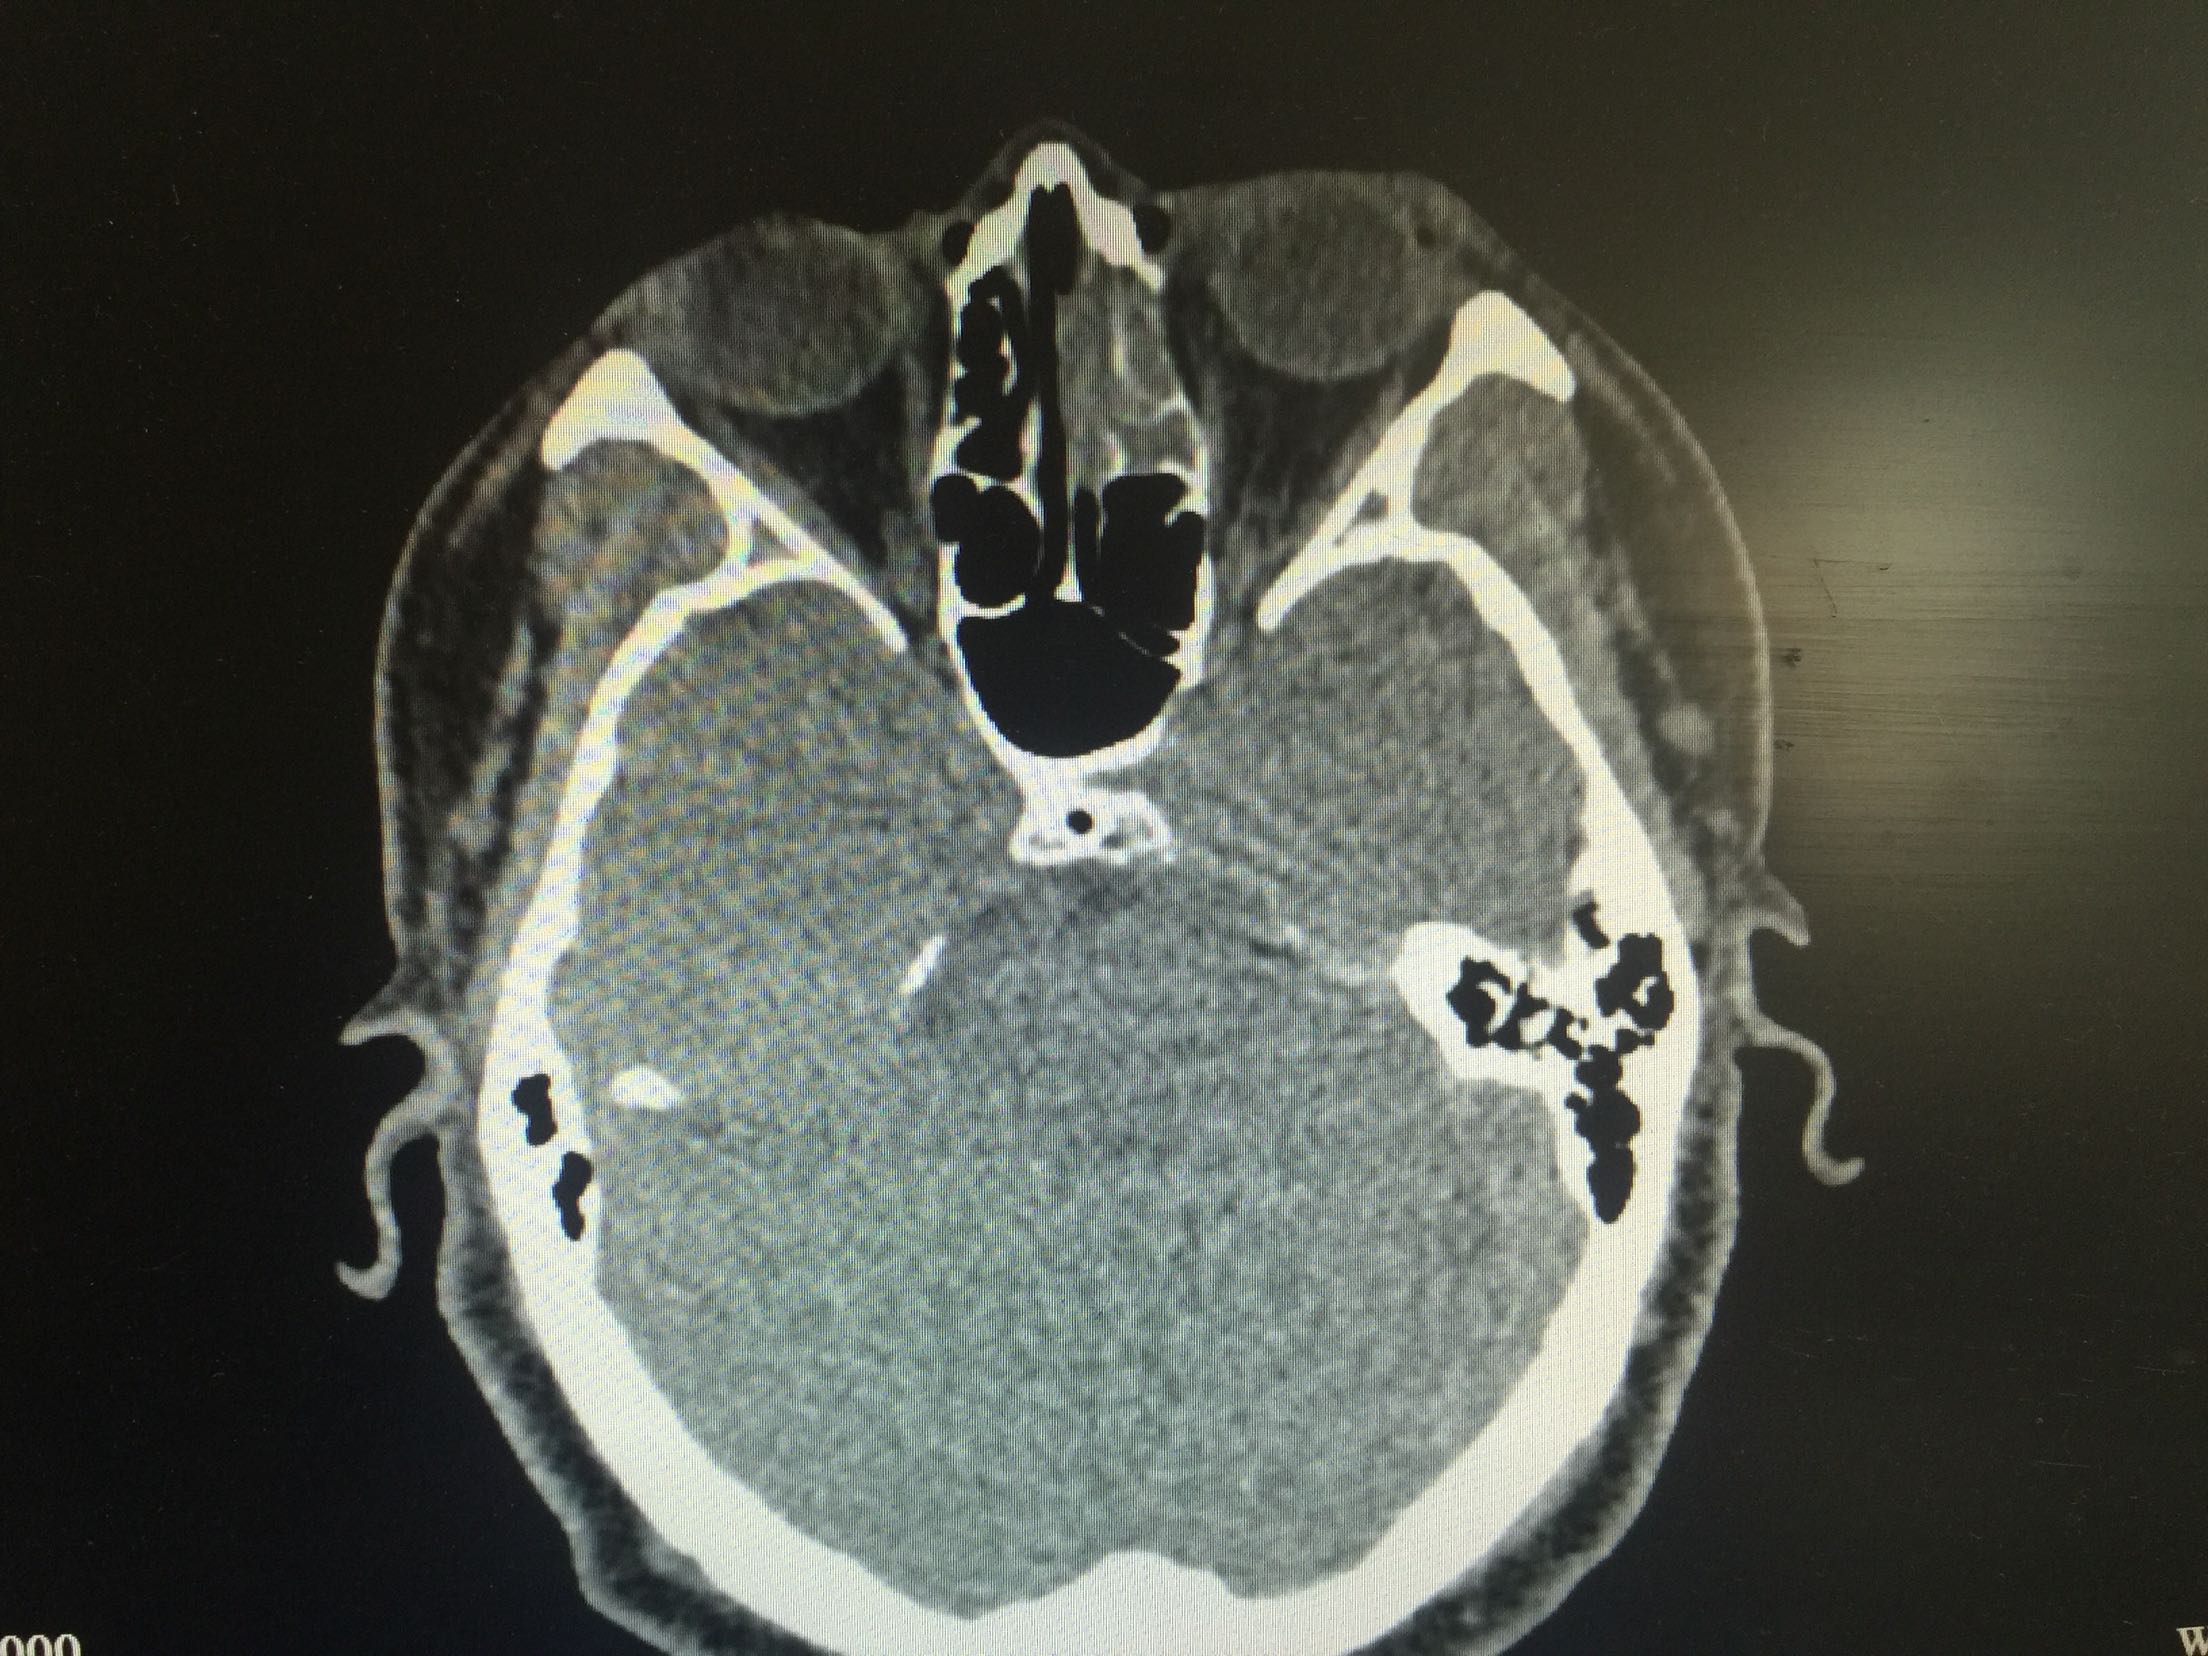

主诉:左侧持续性鼻塞伴流黄涕3个月。 现病史:患者3月前“感冒后”出现左侧鼻腔持续性鼻塞伴流黄涕,无鼻出血,无打喷嚏,无嗅觉减退,无发热,无复视、视力下降,无牙痛,无面部麻木。无呼吸、吞咽困难。未予重视未治疗。4天前就诊于当地医院,行鼻窦增强CT示“左上颌窦占位性病变,恶性肿瘤可能性大”,为进一步诊疗,来我院就诊,门诊检查后以“上颌窦肿物(左)”收入院。患者自发病以来,精神状态良好,食欲良好,睡眠良好,大小便正常,体重无明显变化。 既往史:既往体健。 个人史:无特殊 家族史:无特殊

查体:鼻腔黏膜慢性充血,双侧下鼻甲、中鼻甲肥大。鼻内镜:左侧中鼻道可见少量息肉样新生物。鼻窦冠状位CT:左侧上颌窦占位性病变,不排除内翻性乳头状瘤。